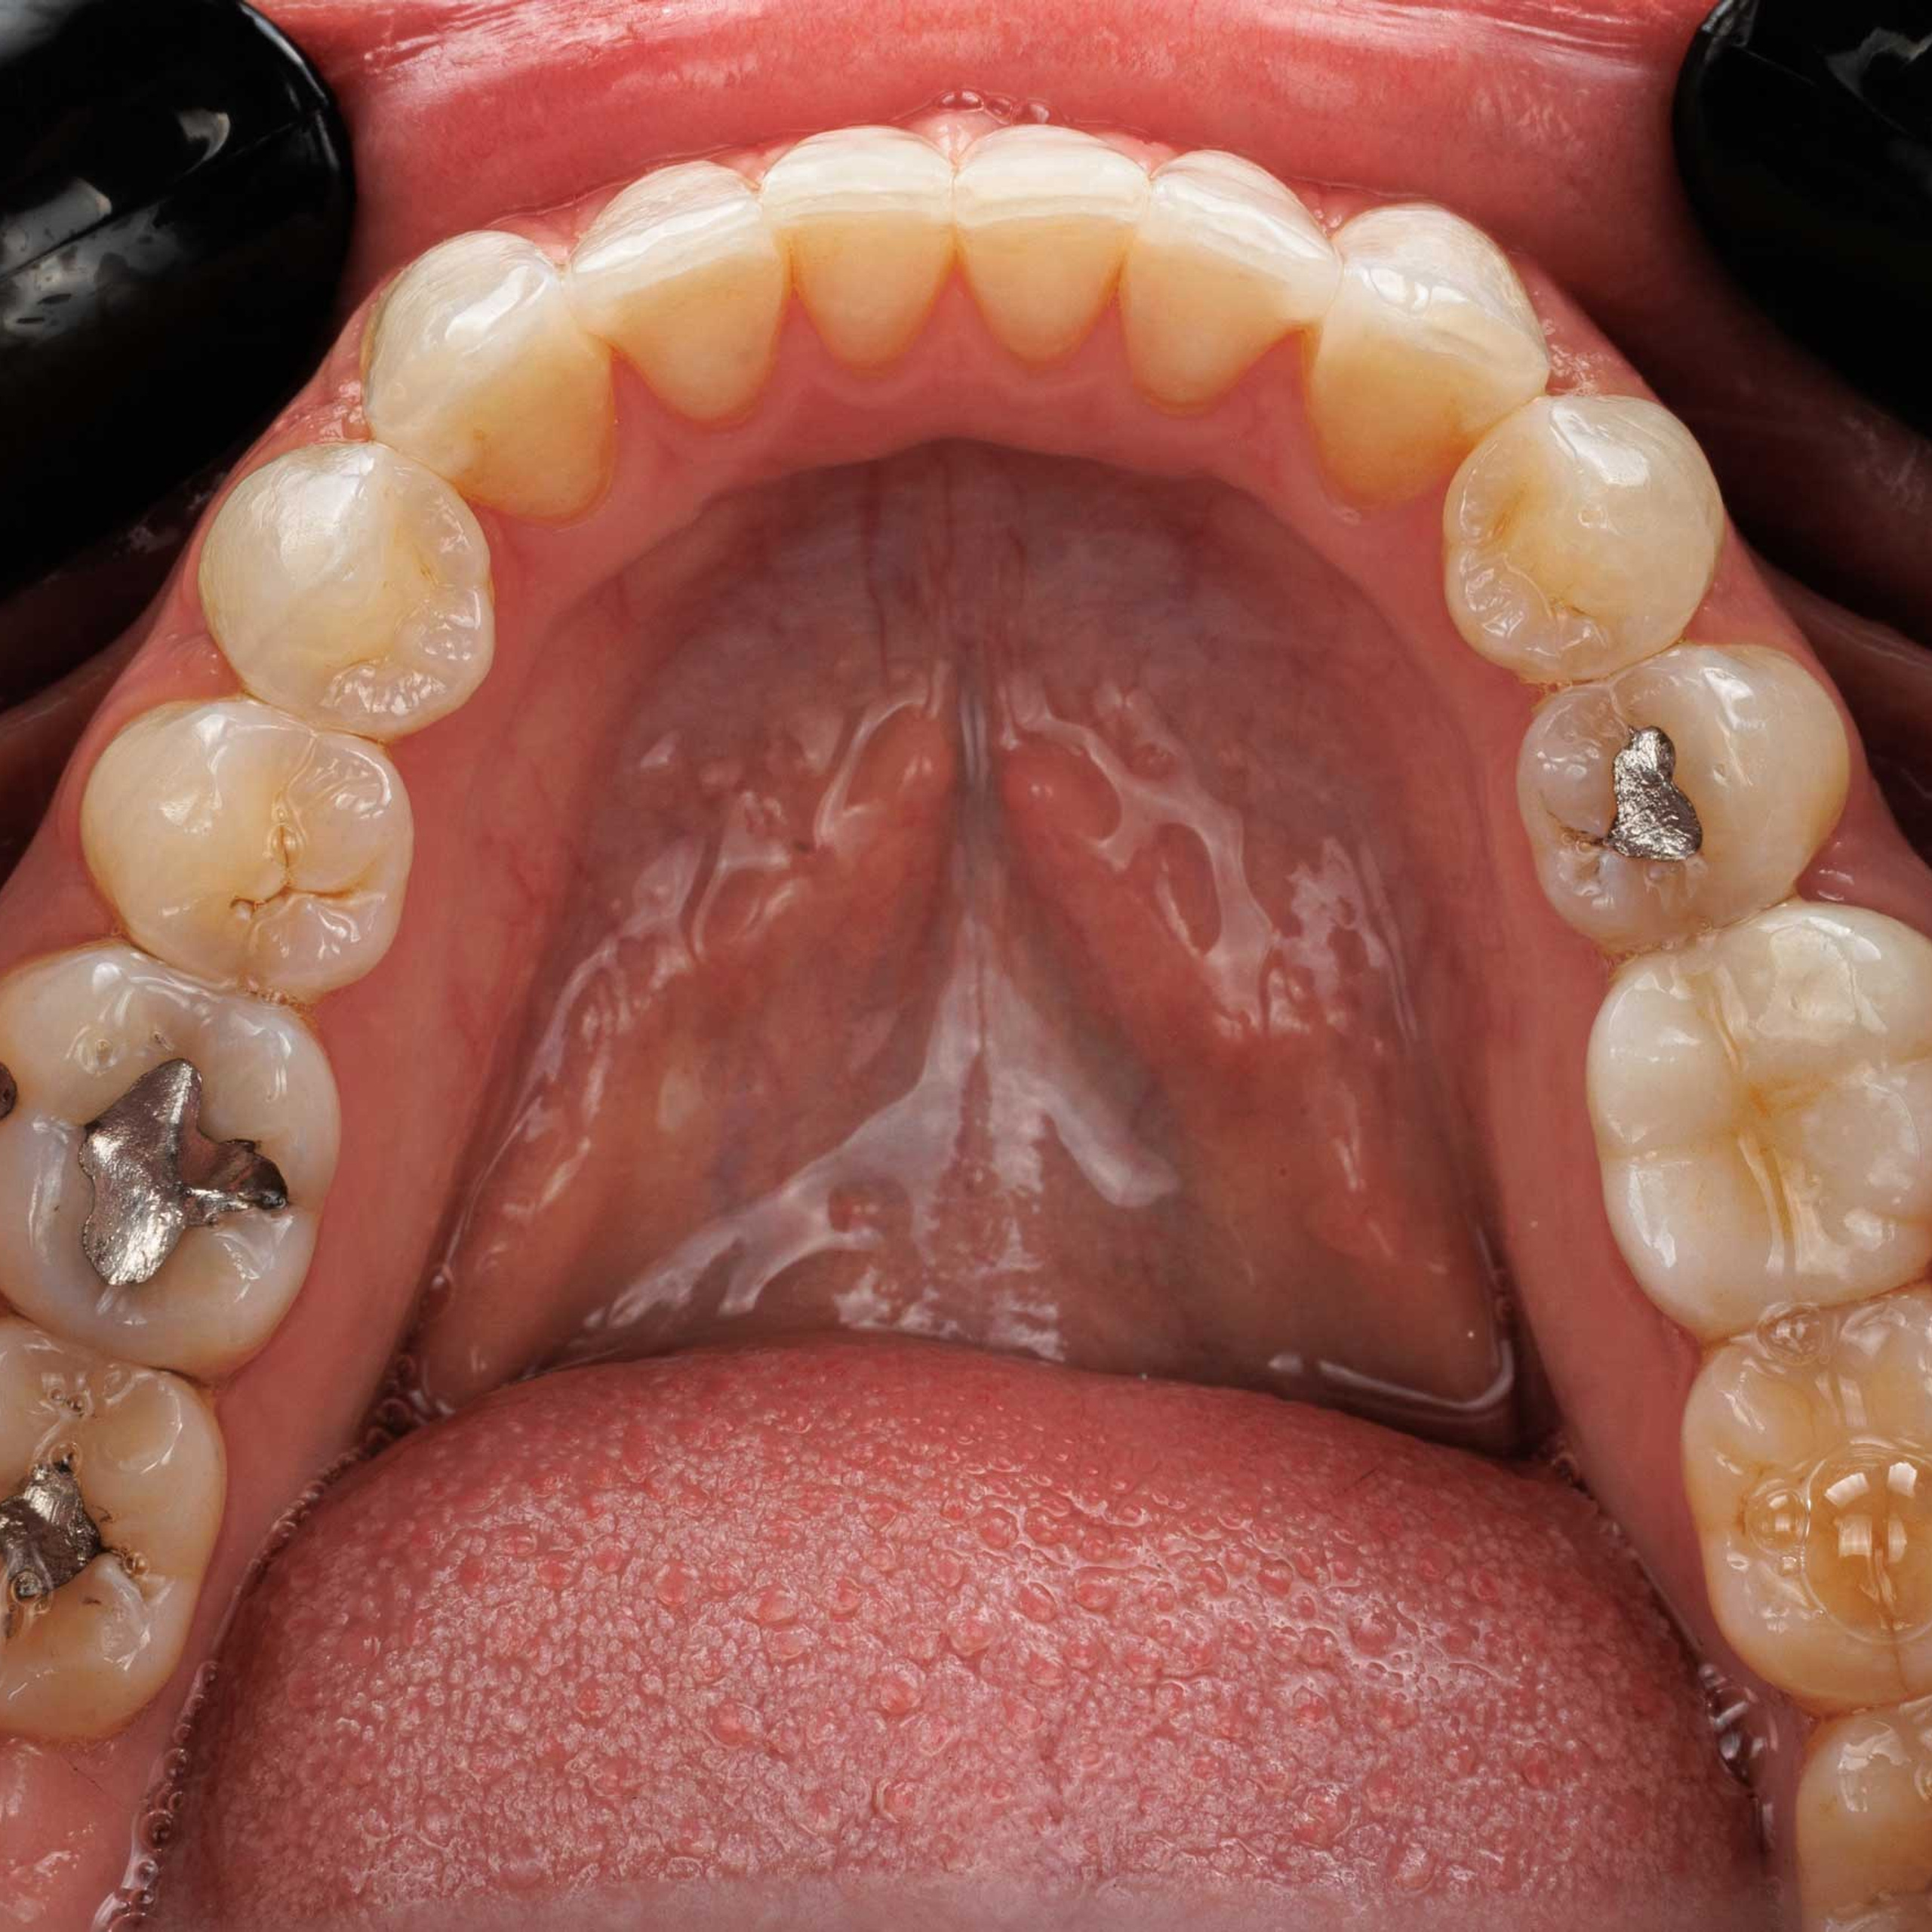

Фотографии учеников до обучения

Фотографии после обучения